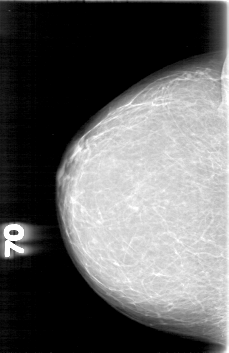

D_4003_1.RIGHT_CC

RIGHT_CC LINES 5281 PIXELS_PER_LINE 3421 BITS_PER_PIXEL 12 RESOLUTION 43.5 NON_OVERLAY